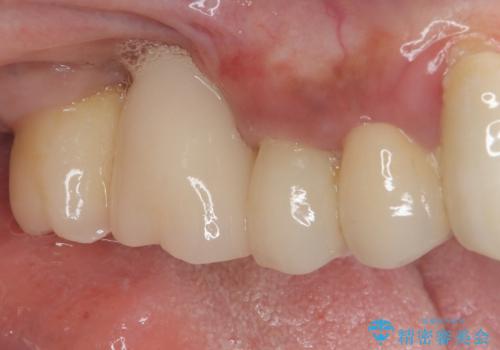

インプラントの初期固定も埋入後の生着もスムーズであったので、埋入から3ヶ月で無事に治療を終えることができました。